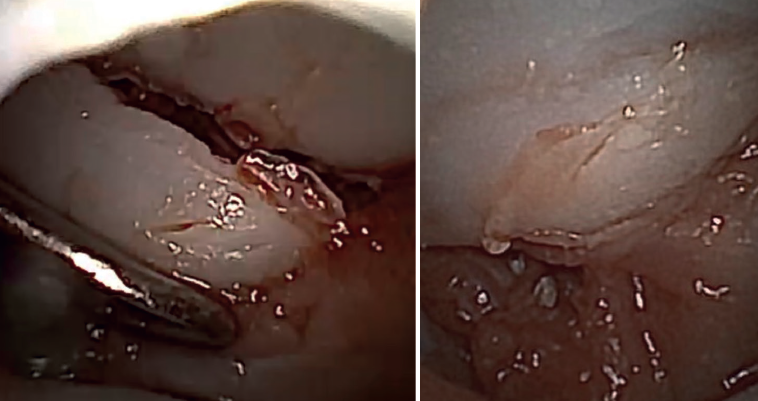

We begin complete evacuation of the fracture hematoma and the synovectomy. This allows inspection of the joint and better identification of the fracture pattern, as well as correct visualization of all the structures.

The free osteochondral fragments can be removed with grasping or mosquito forceps.

The main fragments are reduced with the aid of a palpator or a small blunt dissector. External reduction of the fragments may be necessary, especially when they are impacted in the centre of the articular surface. This is especially common at the base of the proximal phalanx. To do this, we introduce a 1.0 Kirschner wire through the fracture site, through an extra-articular "window", and in "joystick" fashion, we lower the impacted fragment. Sometimes it is advisable to check each of the maneuvers using fluoroscopy, which can be positioned perpendicular to the arm or in the traditional manner, which requires us to release the hand of the patient in order to perform the check.